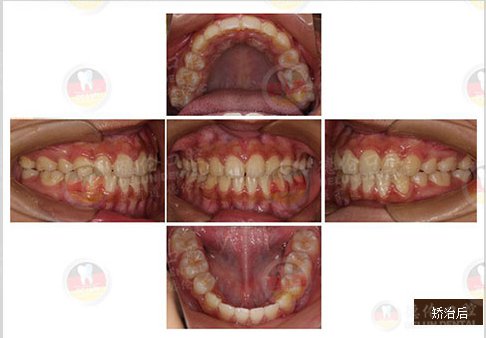

女 13岁

牙齿症状:上下前牙前突、唇倾,上下牙弓散在间隙

矫治方法:SPEED矫治器结合种植钉、整体内收上下牙弓、改善双牙弓前突以及凸面型侧貌